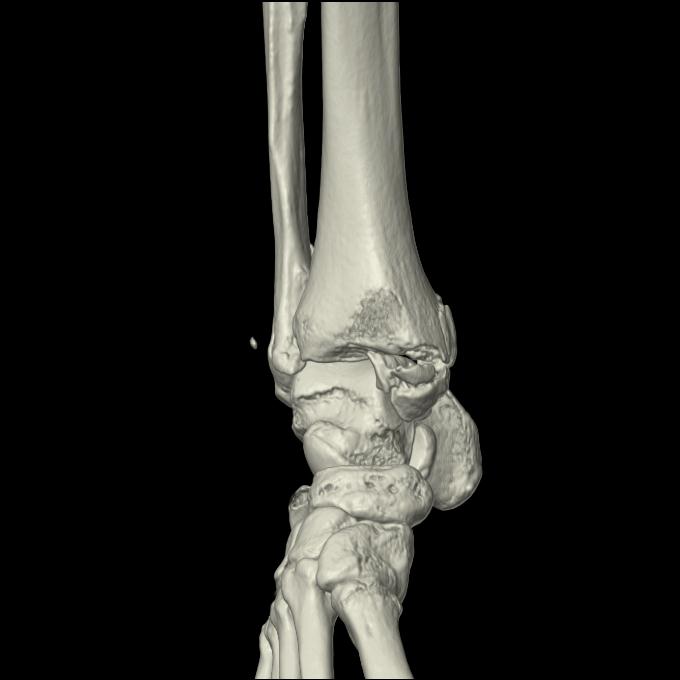

102755 1/4 2R 1/15 2R 右足関節 68歳女性 右三果脱臼骨折